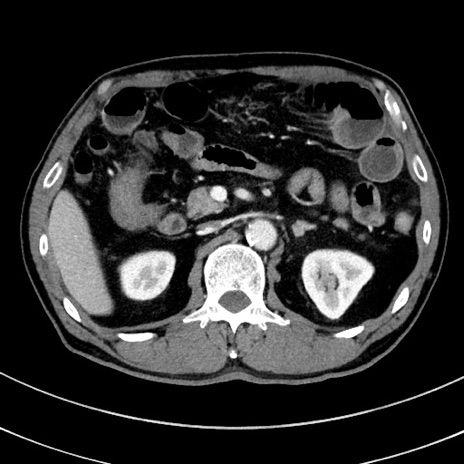

症例8(横断像)

【症例】 60歳代男性

【主訴】 黒色吐物

【現病歴】 4日前から嘔気自覚、2日前の朝食後にも嘔気あり、自分で手で嘔吐反射起こし嘔吐したところ血が混ざっていたため受診。

【既往歴】 5年前汎発性腹膜炎を伴う急性虫垂炎で手術、高血圧、前立腺肥大症、高脂血症

【身体所見】 腹部正中に手術癩痕あり 腹部平坦・軟圧痛なし膨満感あり

【データ】WBC 8400、CRP 4.54